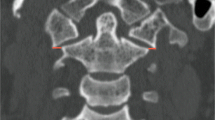

Osteopathia striata with cranial sclerosis (OSCS) is a rare but well-described pathology characterized by abnormalities in bone deposition in the axial and cranial skeleton as well as other abnormalities and associated deficits. These skeletal abnormalities can lead to significant intra-operative challenges for the surgeon and influence outcomes for the patient. In this report, we present a case of a patient with OSCS who was involved in a traumatic motor vehicle crash and underwent posterior cervico-thoracic fusion for a T4 chance fracture. Bony abnormalities in the cervico-thoracic spine presented a significant operative challenge due to alterations in bony anatomy and bone architecture. This case serves as an example of the challenges that the spine surgeon faces when dealing with OSCS, and highlights the differences between OSCS and commoner skeletal hyperplasias such as osteopetrosis.